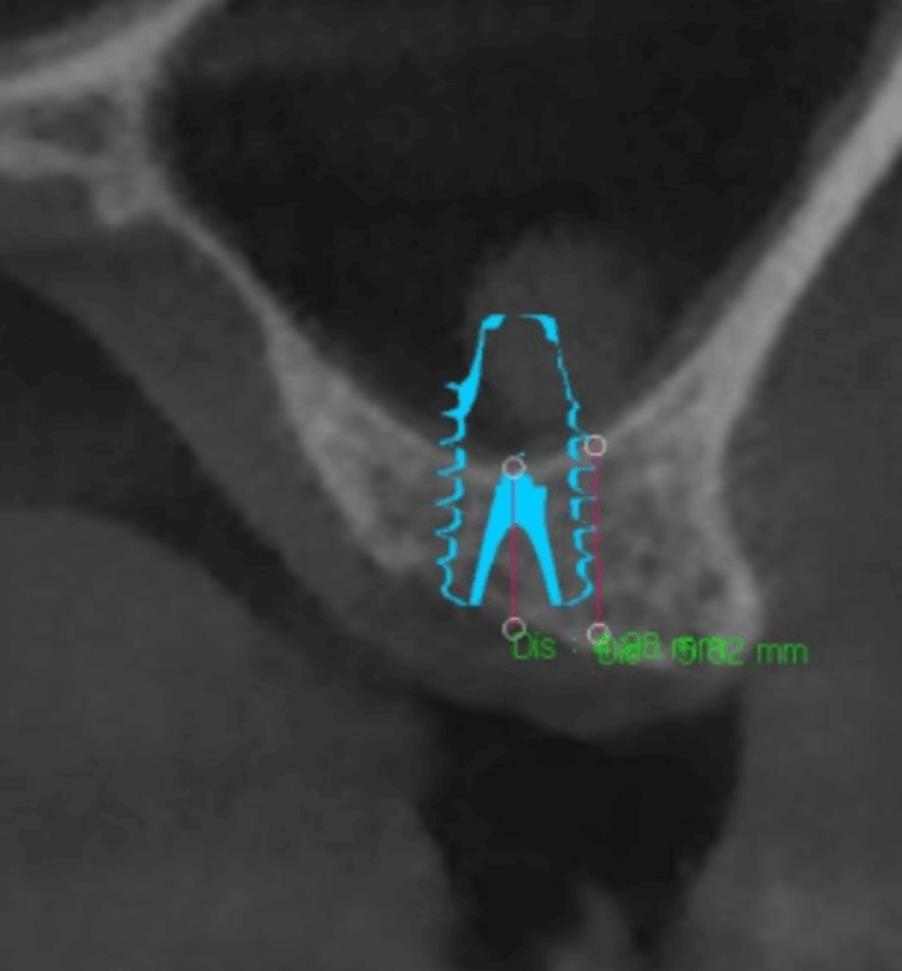

수술 전 CT – 뼈 높이가 부족해 상악동 거상술 필요 소견

수술 후 CT – 상악동 뼈가 안전하게 거상된 모습